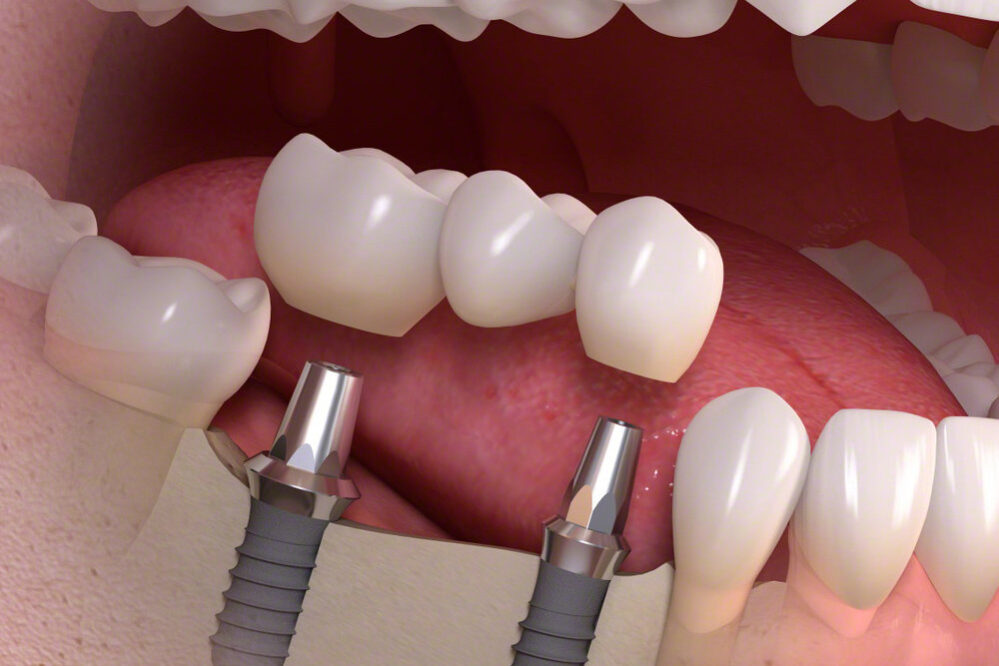

Los prostodoncistas devuelven la estética, la función y la comodidad por medio de elementos artificiales (prótesis). El objetivo es restaurar dientes dañados, reponer dientes ausentes y mejorar la estética del paciente (mediante prótesis fijas o removibles según las necesidades de cada paciente).

En Clínica Dental Marin le informaremos de cuáles son las mejores opciones de tratamiento en tu caso para reponer uno o varios dientes perdidos, o dañados.